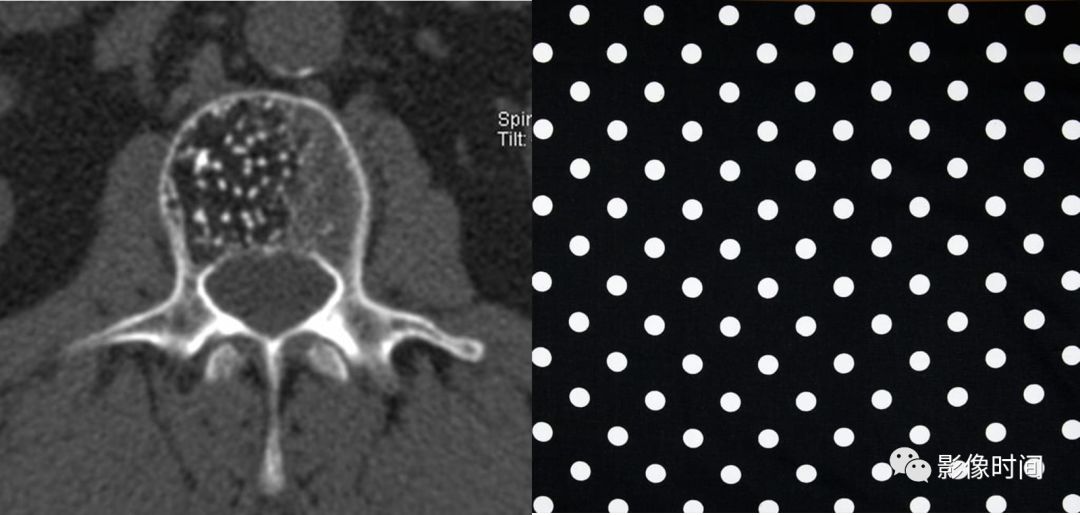

11圆点征

圆点征(Polka-dot sign)

圆点征指的是在横断面图像上,椎体骨松质呈粗大网眼状改变,残留骨小梁增粗呈稀疏排列的多发粗点状高密度影。此征象多提示脊柱血管瘤。

典型病例

胸椎血管瘤。A.CT 横轴位骨窗示椎体右侧部骨小梁稀疏粗大,呈圆点征;B. 矢状位 MPR 图像呈现栅栏征。